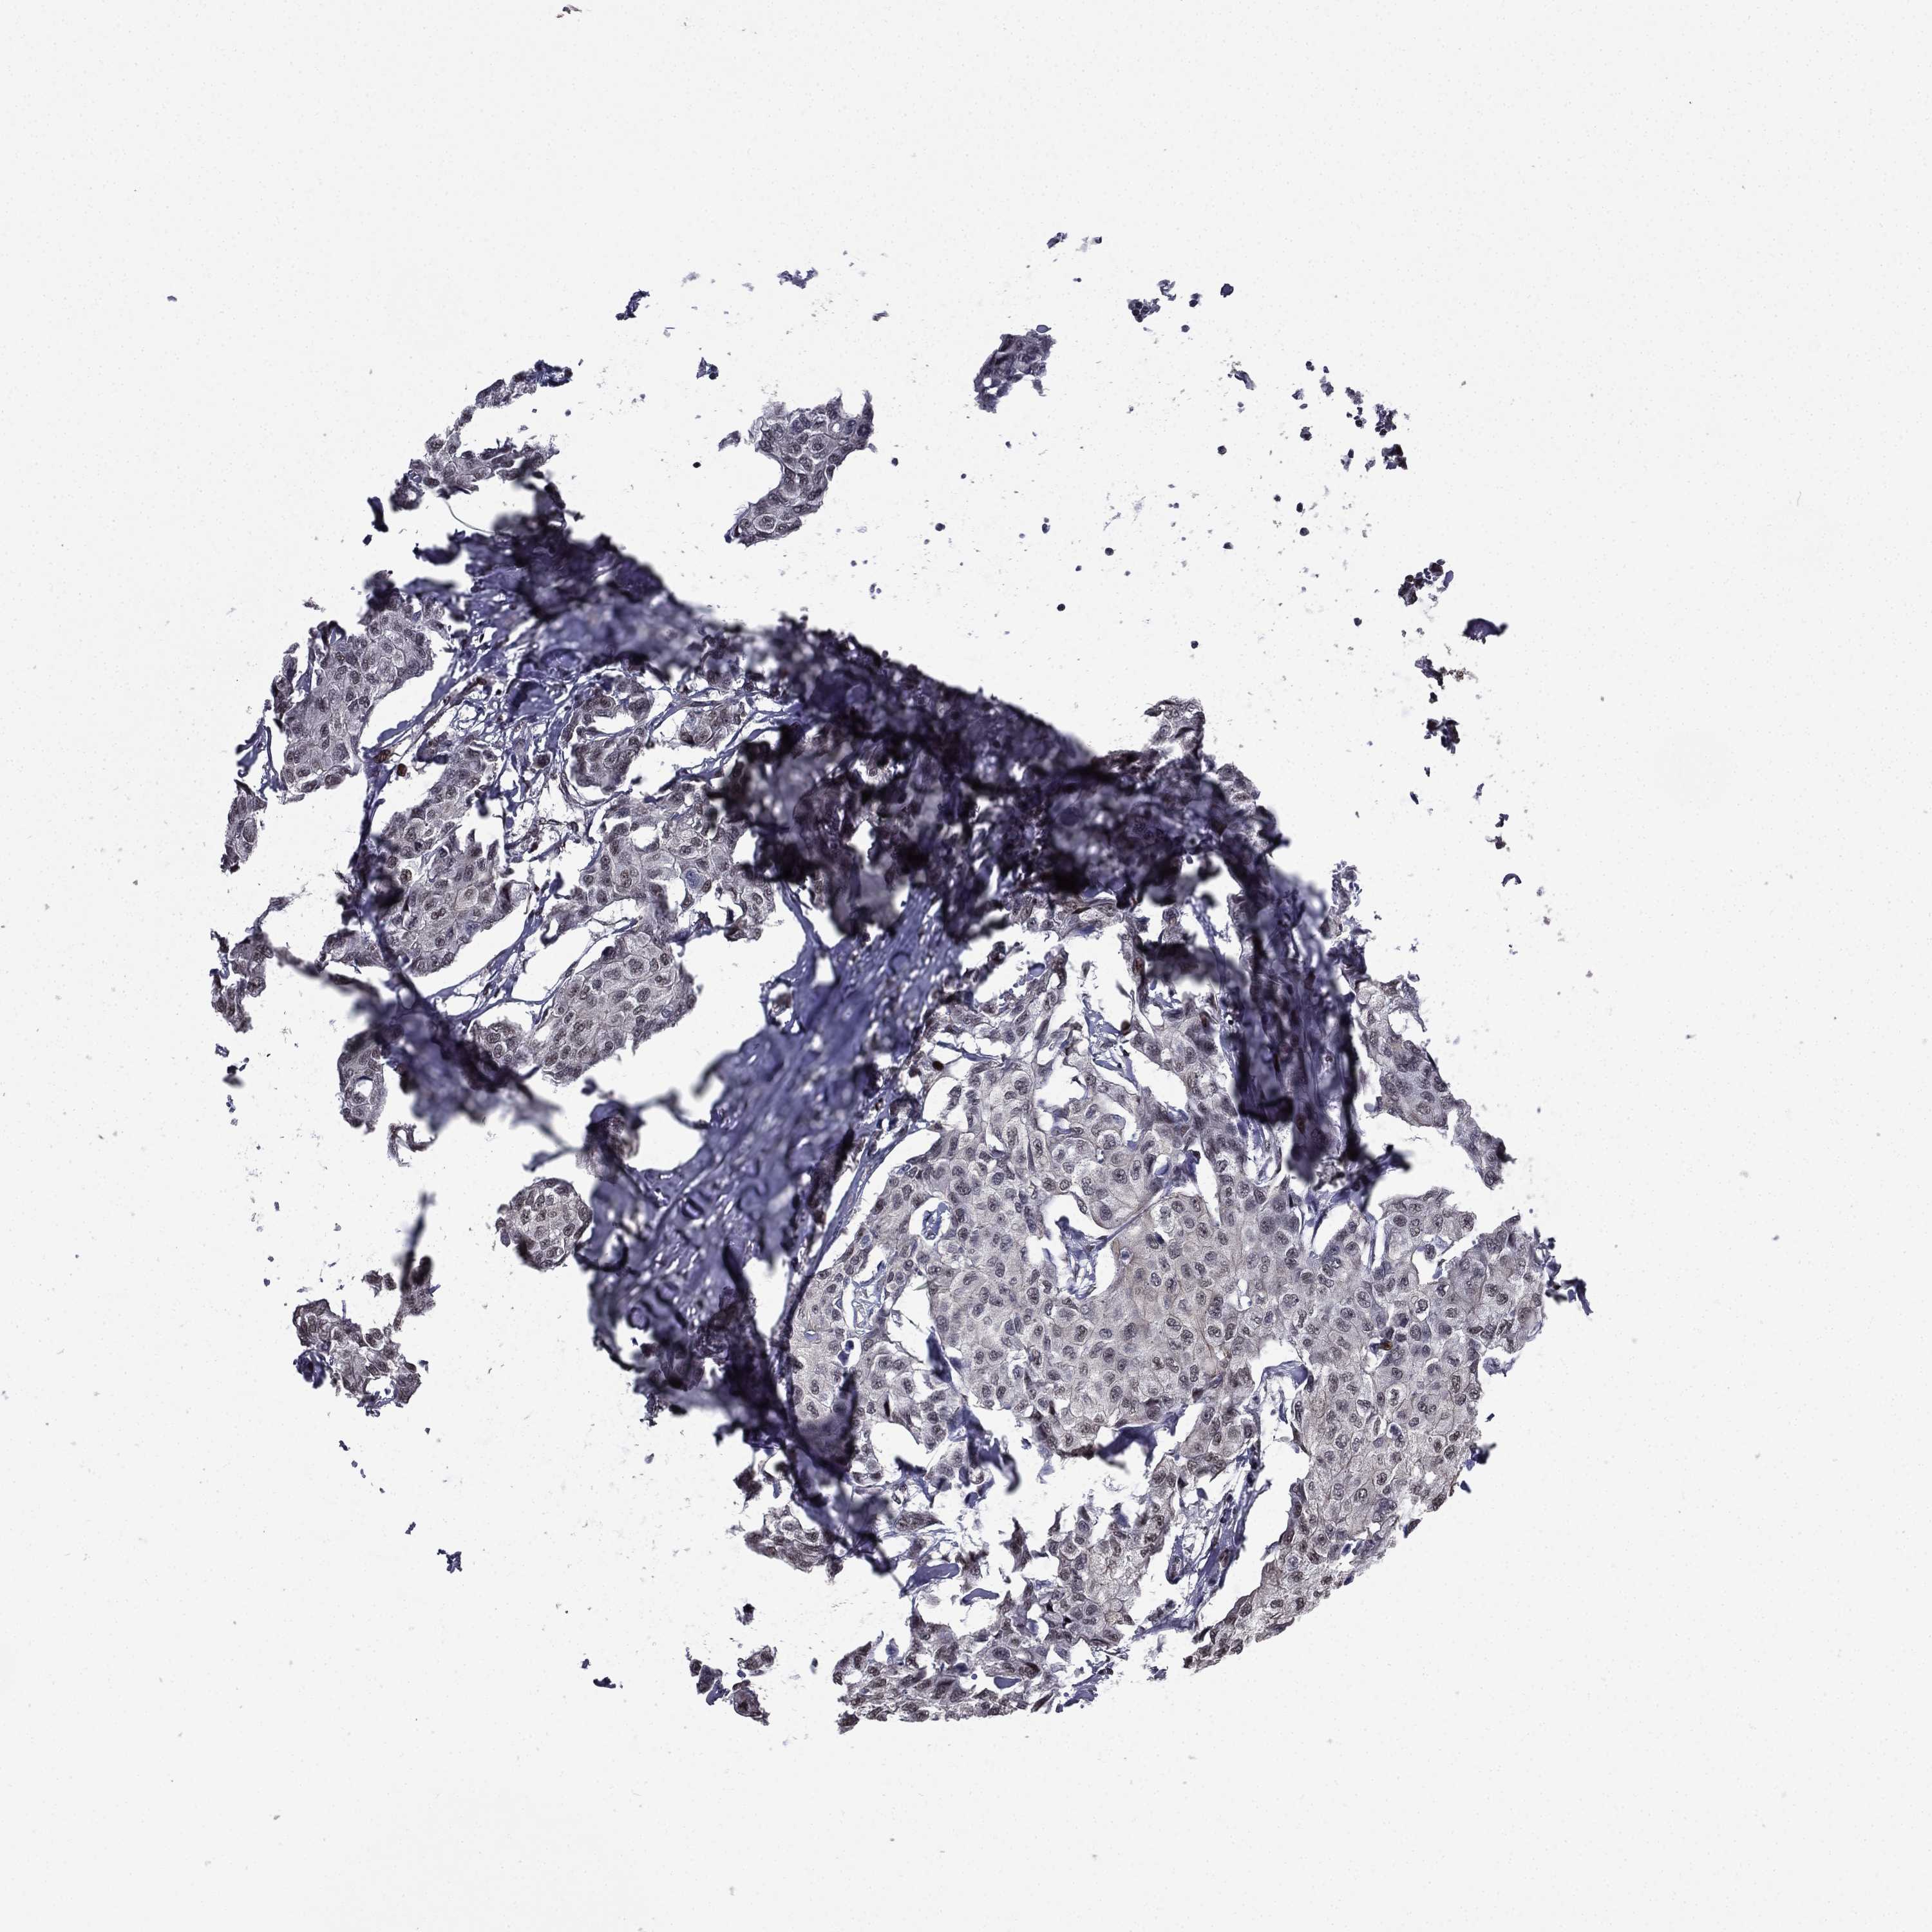

CANCER BREAST CANCER Show tissue menu

BRCA TCGA BRCA VALIDATION PROTEIN EXPRESSION